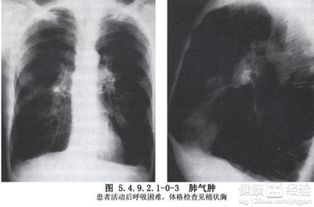

肺氣腫早期常無癥狀或僅感到氣促、胸悶、呼氣不暢。隨病情發(fā)展會感到進行性呼吸困難,上樓時氣喘吁吁,心慌氣促,胸部呈圓桶狀。由于肺通氣和換氣功能障礙,??稍斐扇毖?、口唇、指甲有紫紺,可形成槌狀指,在寒冷季節(jié),特別是抵抗力和肺功能較差的老年病人,易合并肺部急性感染,加重病情,可發(fā)生呼吸衰竭。

肺氣腫是指終末細(xì)支氣管遠(yuǎn)端(呼吸細(xì)支氣管、肺泡管、肺泡囊和肺泡)的氣道彈性減退,過度膨脹、充氣和肺容積增大或同時伴有氣道壁破壞的病理狀態(tài)。按其發(fā)病原因肺氣腫有如下幾種類型:老年性肺氣腫,代償性肺氣腫,間質(zhì)性肺氣腫,灶性肺氣腫,旁間隔性肺氣腫,阻塞性肺氣腫。